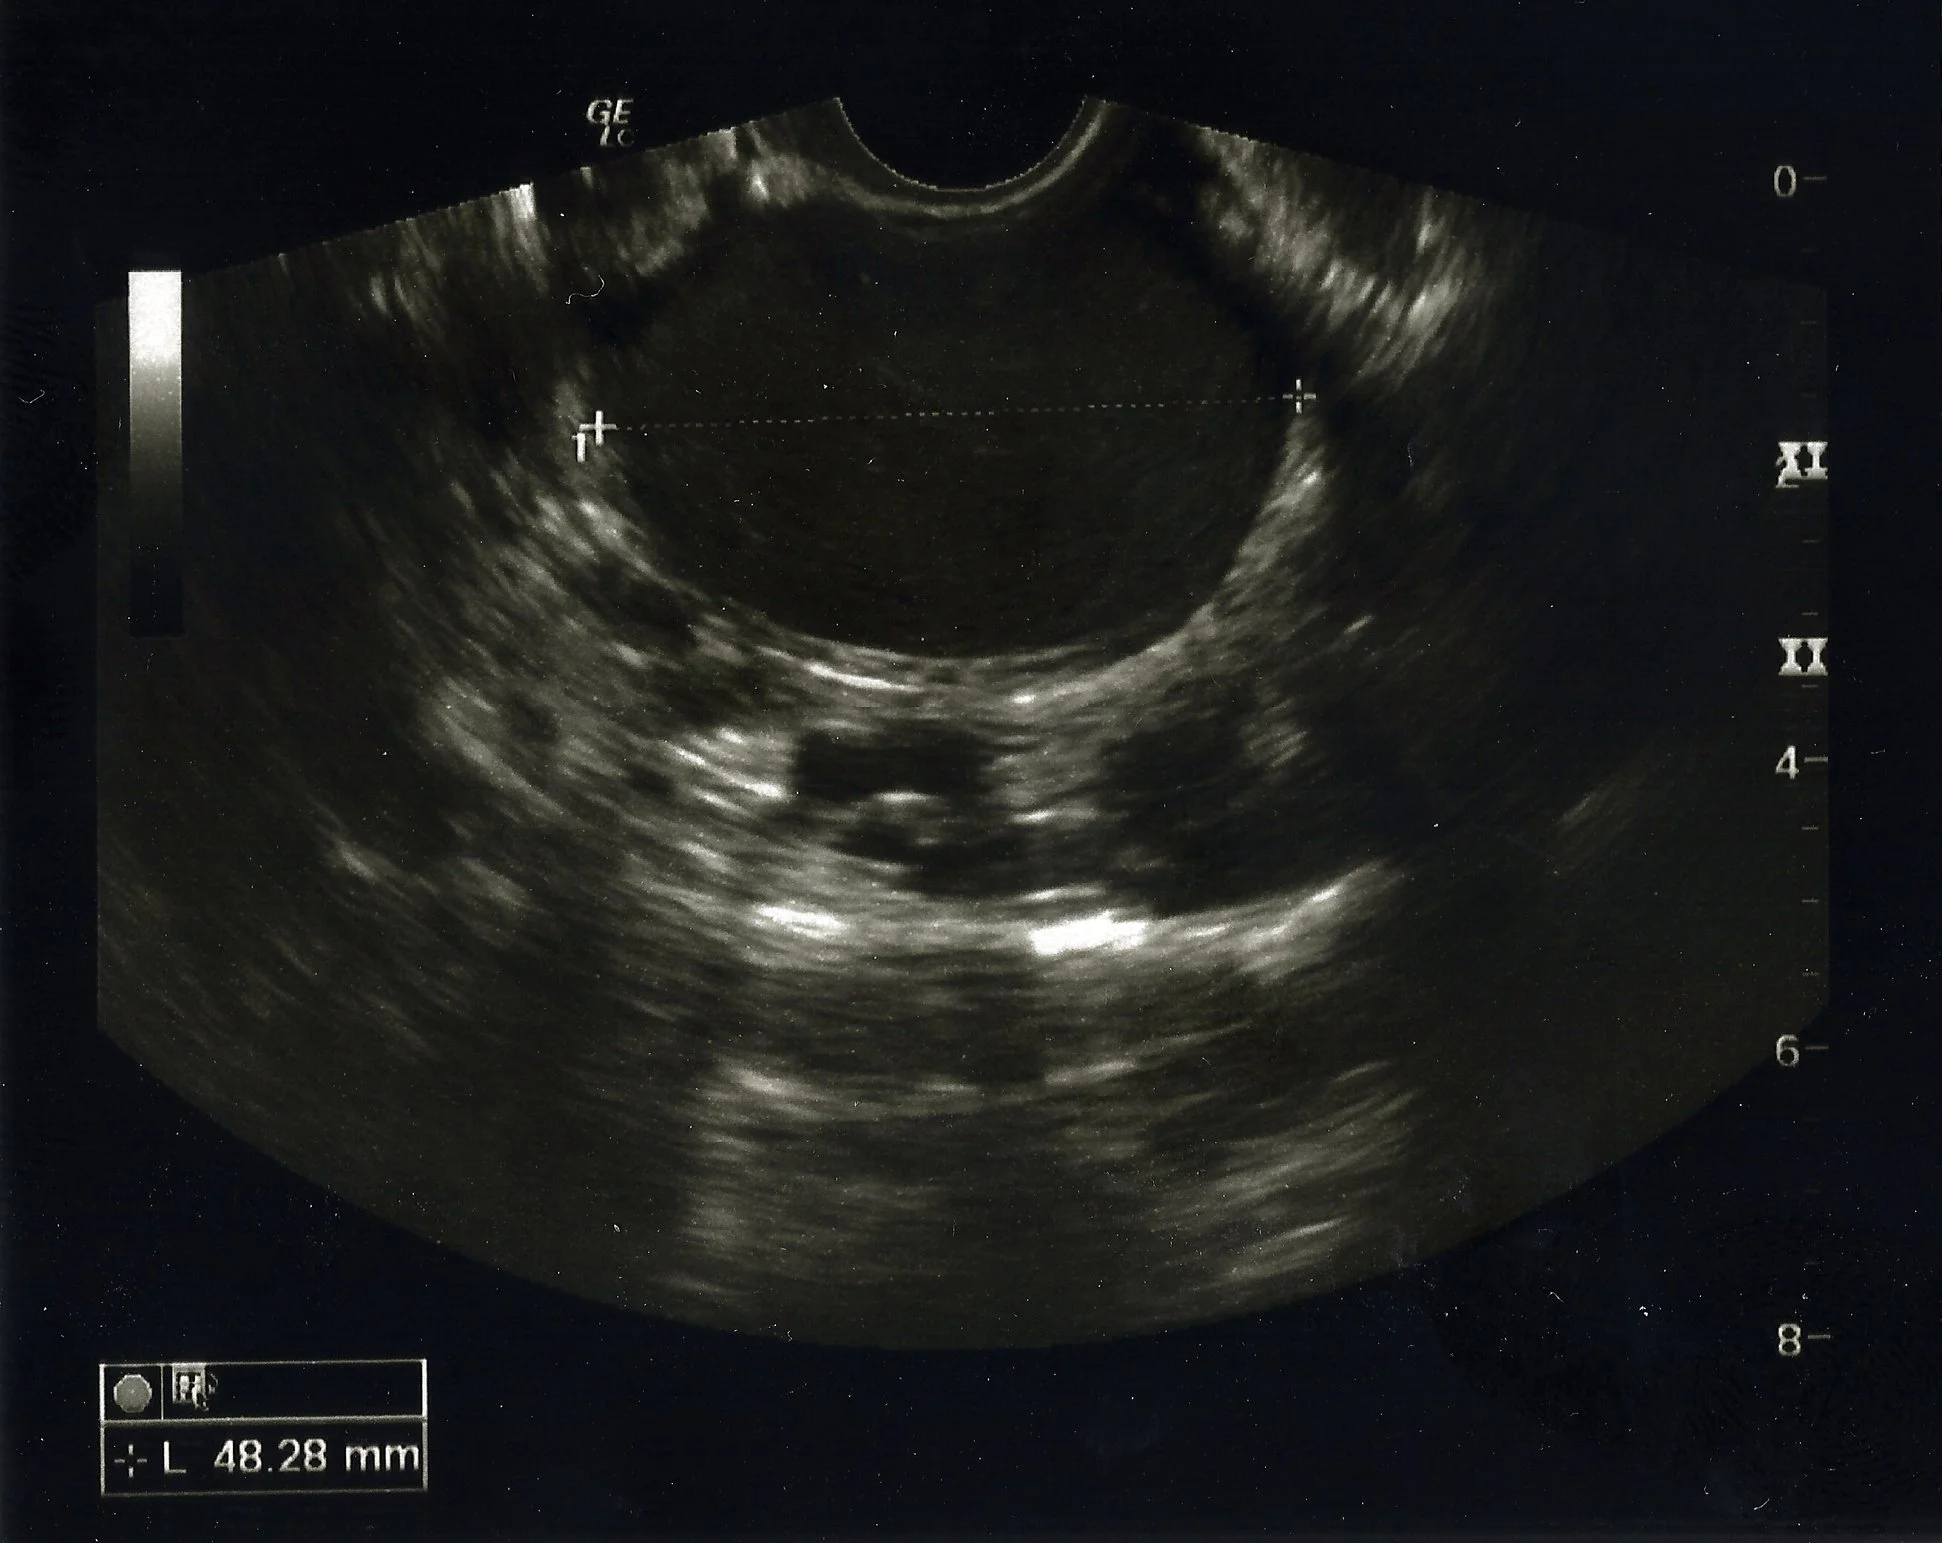

Obtaining a Diagnosis

Endoscan Health is led by Mr Tom Holland, Consultant Gynaecologist, specialising in endometriosis diagnosis and surgery.

We are focused on reducing the time to an accurate diagnosis.